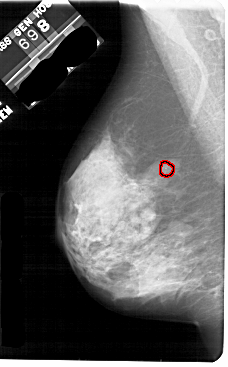

A_1844_1.RIGHT_MLO

RIGHT_MLO LINES 5491 PIXELS_PER_LINE 3046 BITS_PER_PIXEL 12 RESOLUTION 43.5 NON_OVERLAY

FILE: A_1844_1.LEFT_MLO.OVERLAY

TOTAL_ABNORMALITIES 1

ABNORMALITY 1

LESION_TYPE CALCIFICATION TYPE PLEOMORPHIC DISTRIBUTION CLUSTERED

ASSESSMENT 4

SUBTLETY 3

PATHOLOGY BENIGN

TOTAL_OUTLINES 1

BOUNDARY